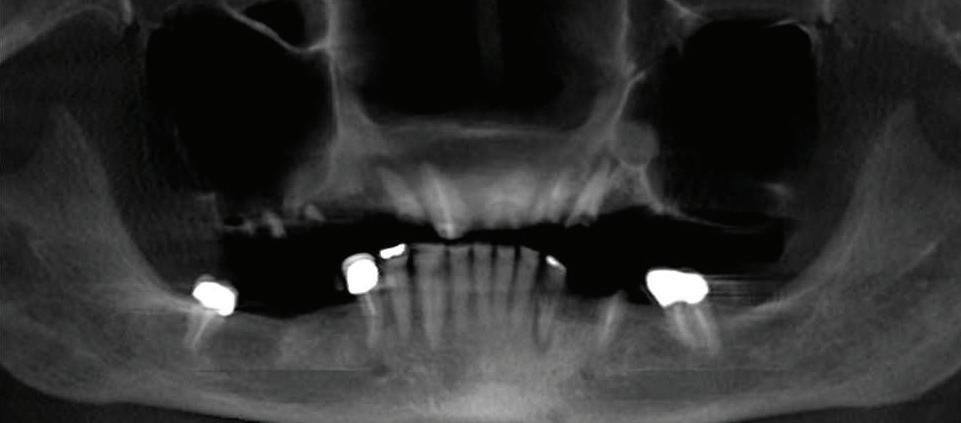

Can just four implants replace all of the teeth on the top or the bottom of your mouth? Thanks to advances in dental implant technology, that answer is a resounding yes.

Tooth loss is extremely common among adults, especially as we age. Rather than living with the discomfort and hassles of dentures, many people are opting for what is called “all-onfour” dental implant restoration.

An implant is a small titanium

screw that fits inside your jawbone and replaces the root-part of a missing tooth. Minor surgery is required to insert the implants. Once the implant is in place, a crown is attached to give you a highly realistic-looking and functional prosthetic tooth.

You do not need a dental implant for each and every one of your missing teeth. All you need is four precisely placed implants on the top of your mouth, and four on the bottom, to restore your full smile. That’s the beauty of the all-on-four. And because the implant is made of titanium, it has the unique ability to fuse to living bone and function as part of it. So eventually, the dental implant becomes part of the jawbone and serves as a strong, longlasting foundation for your new teeth.

Besides ensuring that your implants are permanently fixed in place, this bone fusion has another important benefit: it prevents future bone loss in the jaw. This helps to maintain a more youthful facial structure – and better

Please see “All-On-Four,” page 63